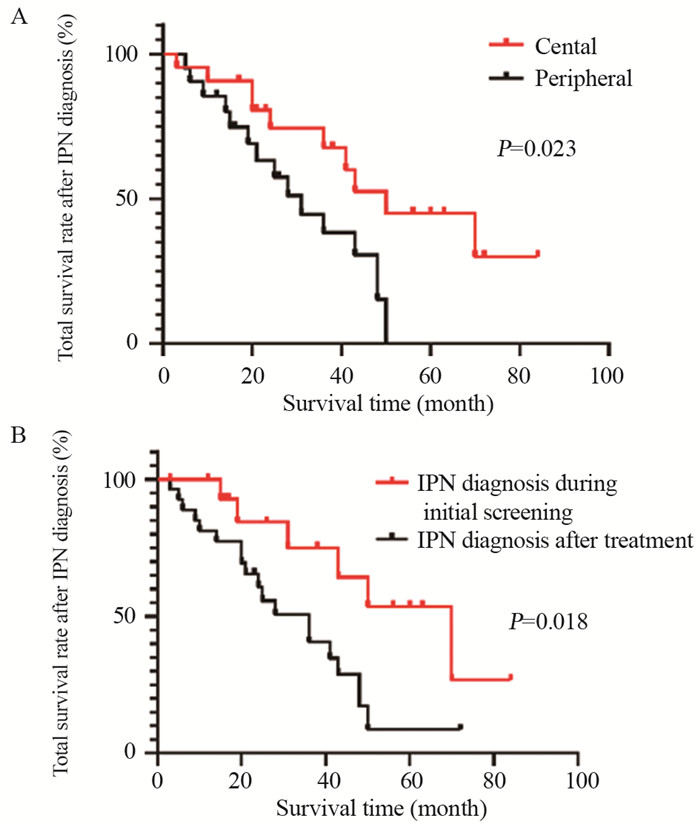

43例恶性转归的IPN高级别STS患者中,25例死亡、18例存活,平均生存期为28.442±20.041个月。将患者性别及IPN的CT影像学特征对IPN诊断后生存期的影响进行单因素分析。结果显示,IPN位置以及结节发现间期与恶性转归的IPN高级别STS患者的IPN诊断后生存期相关,见表 2、图 1。进一步将表 2中P<0.150以及文献中既往已报道与高级别肉瘤患者预后相关的因素纳入到多因素分析中。结果显示年龄(HR=1.047, 95%CI: 1.007~1.088)与结节发现间期(HR=3.194, 95%CI: 1.052~9.694)是影响伴恶性转归的IPN高级别STS患者IPN诊断后生存期的独立因素,见图 2。年龄较大以及治疗后发现IPN导致患者具有更差的生存预后。

表 2 影响高级别STS患者IPN诊断为恶性IPN后生存期的单因素分析Table 2 Univariate analysis of survival after IPN diagnosis in patients with high-grade STS and malignant IPN